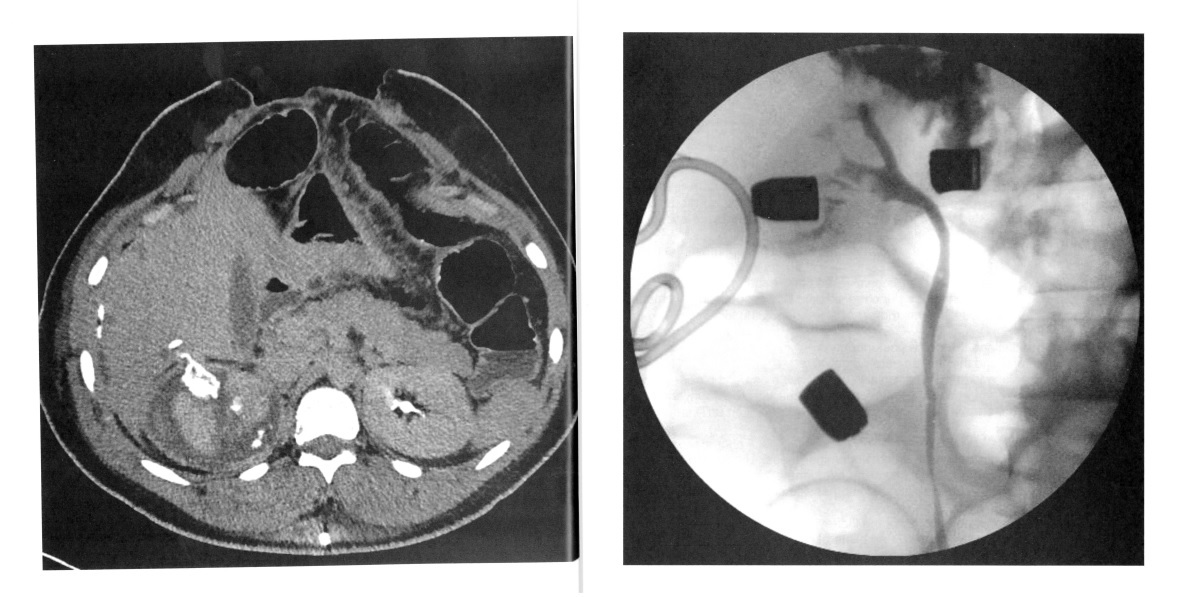

A 24-year-old man is shot in the right flank and sustains a grade 5 renal injury and extensive liver and bowel injury. During exploration, his liver and bowel injuries are stabilized and a nonpulsatile right retroperitoneal hematoma is identified with no intervention . One week after exploration, he develops increased drainage from a perihepatic drain. Creatinine of the drainage fluid is 8 mg/di. CT scan and retrogradepyelogram are shown. The next step is:

The patient has a delayed urine leak following high velocity penetrating renal trauma. CT scan and retrograde pyelogram reveal a urine leak. The next step is ureteral stent and urethral catheter drainage to prevent reflux of urine retrograde into the stent which may potentiate the leak and result in infection of the retroperitoneal hematoma. Ureteral stent placement may allow for resolution of the leak without operative intervention. The patient’s recent history of shattered kidney along with liver and bowel injury placement of a percutaneous nephrostomy tube would result in increased risk for infection of the perinephric hematoma and maybe difficult to place and maintain in the proper position due to the renal injury. Exploration of the right kidney is not ind icated at this time.